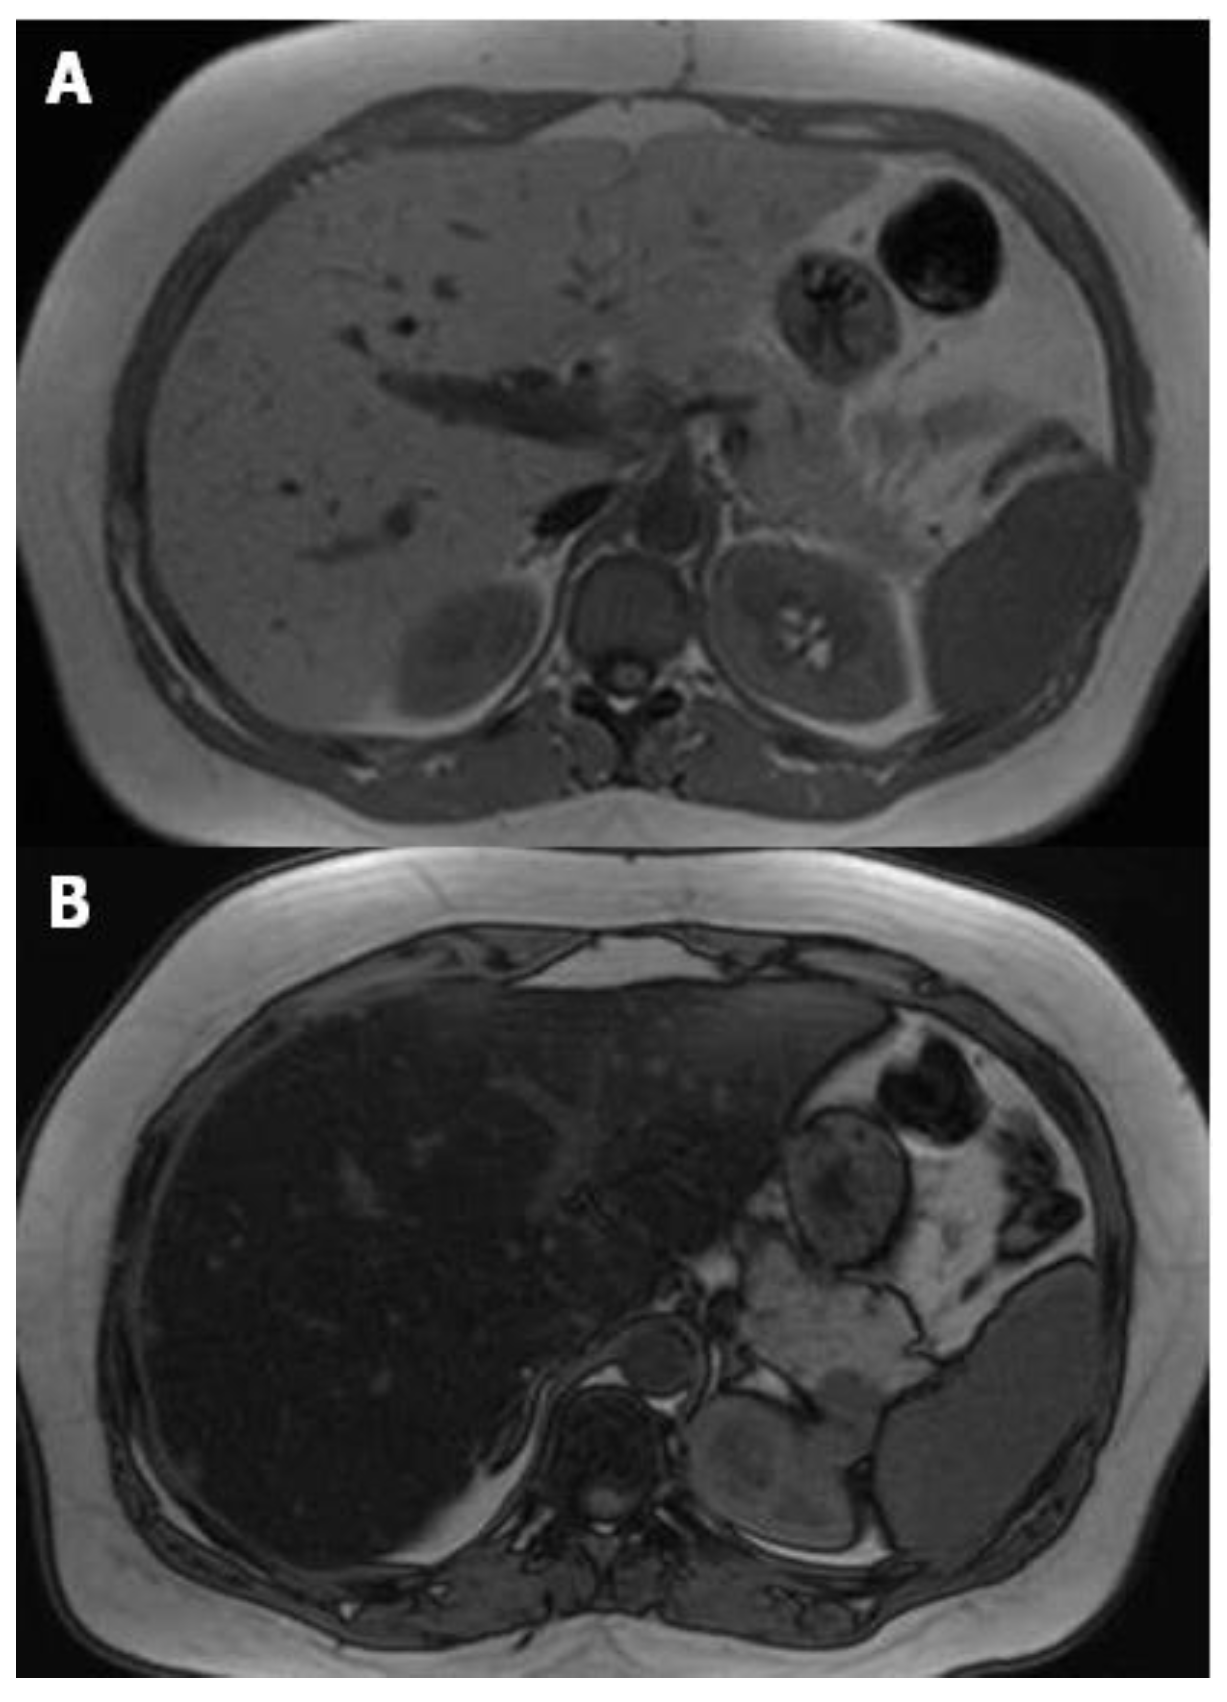

Different methods can be performed for the evaluation of liver steatosis by magnetic resonance imaging (MRI), but the most widely preferred method is based on chemical shift imaging [14,15]. This technique is based on the different precession of protons linked to water and triglyceride molecules. Two sets of gradient-echo images of the liver are obtained, and echo-time-dependent signal interference between fat and water is considered. On in-phase echo-time, water and fat signals add up and therefore, the total signal intensity is higher. On out-of-phase echo-time, water and fat signals cancel out each other and consequently the total signal intensity decreases. Healthy liver has no difference in signal intensities between the in-phase and out-of-phase images, however, in the case of fat storage, the liver signal intensity diminishes on the out-of-phase image (Figure 3). This imaging method is reliable in the absence of magnetic field non-homogeneity and iron deposition. The main drawback is that the quantity of water and fat can affect their signals. This can be managed by acquiring new images with variable T1-weighting, through the application of two flip angles. High-flip-angle imaging is desirable for uncovering small amounts of fat in tissues that include mainly water, while low-flip-angle imaging should be applied for revealing small amounts of water in fat-rich tissues [16].

Figure 3.

MR T1-weighted images with different echo times (TE) 4.2 (A) and 2.1 (B), show a marked drop of signal intensity in the out-of-phase image (B) which is a sign of severe steatosis.